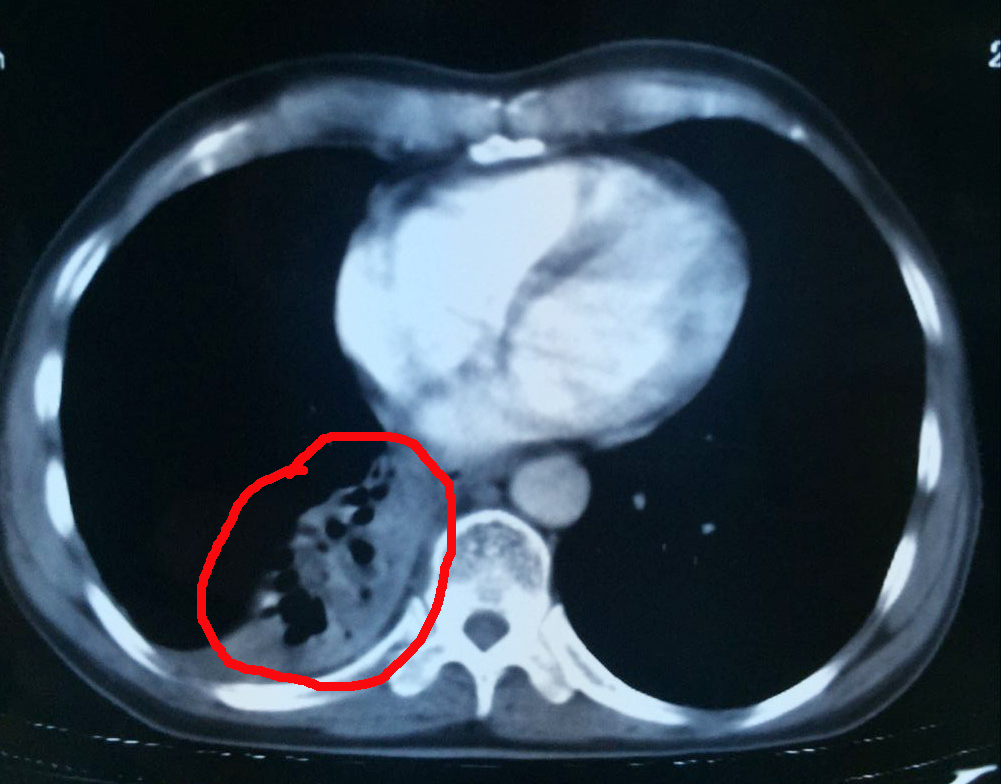

肿瘤治疗中

6月28日,杨清贵接受了介入治疗,手术顺利。术后杨清贵没有明显的不适症状,24小时后正常行走。为进一步杀灭肿瘤,杨清贵又接受了氩氦刀治疗。据了解,氩氦刀适用于各种类型的实体瘤,其治疗原理是在CT的引导下,将冷冻穿刺针插入肿瘤里,注入氩气,使冷冻针尖迅速降温至零下140-160摄氏度,将肿瘤冷冻成冰球,再注入氦气使冷冻针尖迅速升温至40摄氏度左右,如此反复两到三个循环,让肿瘤细胞崩解凋零。

术前的杨清贵心情十分忐忑,但听了医生一番话后又恢复了平静。“林菁医生耐心地跟我们解释了治疗有哪些风险,如肿瘤靠近肺门以及气管,冷冻治疗可能会造成出血、咳血、气胸等,但很快又给我们服下定心丸,‘医院每天都做5-6台这样的手术,手术的专家经验都十分丰富,出现并发症的情况极少。’”张英友说道。据了解,经过近3个月的综合治疗,目前杨清贵的肿瘤几乎全部消失,胃口、睡眠等恢复良好,身体与常人无异。